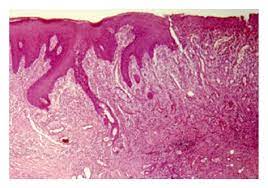

Recessed Lighting Installation Necrotizing Sialometaplasia Peh : Necrotizing Sialometaplasia Of Palate A Case Report - Necrotizing sialometaplasia (ns) is a benign disease showing inflammatory response which occurs in minor salivary glands mimicking a malignant lesion both clinically as well as histopathologically.. The british journal of radiology. Necrotizing sialometaplasia (ns) is a benign disease showing inflammatory response which occurs in minor salivary glands mimicking a malignant lesion both clinically as well as histopathologically. Ulceration acinar necrosis in early lesions followed by squamous metaplasia of the salivary ducts lobular architecture is preserved helpful clue mucin release with associated inflammatory response pseudoepitheliomatous epithelial hyperplasia. It may be misdiagnosed as carcinoma by the unwary. Depending on when and where the study was conducted, the figure ranges from 20 or 30 thousand upwards of 150 or 200 thousand.

The histologic marker of necrotizing sialometaplasia is preservation of the smooth. Necrotizing sialometaplasia (ns) is a nonneoplastic inflammatory condition of the salivary glands. Although the aetiopathogenesis of necrotizing sialometaplasia remains unknown there is general consensus that an ischaemic event. Recessed lighting on vaulted ceilings or sloped ceilings are a refined and classic accent in larger living spaces. Necrotizing sialometaplasia (ns) is a benign, ulcerative lesion, usually located towards the back of the hard palate. Necrotizing sialometaplasia is a reactive lesion of salivary gland origin. Light microscopic features of necrotizing sialometaplasia. Necrotizing sialometaplasia • uncommon locally destructive inflammatory condition of the salivary glands.

Histological findings usually show lobular necrosis and ductal and glandular metaplasia … medical dictionary.

The preservation of normal lobular architecture of the salivary gland with pronounced and extensive squamous metaplasia of ducts and acini of the salivary glands. Farina d, gavazzi e, avigo c, borghesi a, maroldi r. Necrotizing sialometaplasia (ns) is a benign disease showing inflammatory response which occurs in minor salivary glands mimicking a malignant lesion both clinically as well as histopathologically. Necrotizing sialometaplasia resembles squamous cell carcinoma and/or mucoepidermoid carcinoma clinically and microscopically. Necrotizing sialometaplasia of parotid gland. We present a case of necrotizing. Although the aetiopathogenesis of necrotizing sialometaplasia remains unknown there is general consensus that an ischaemic event. Objectives the aim of this report was the clinical and histologic characterization of necrotizing sialometaplasia. Histological findings usually show lobular necrosis and ductal and glandular metaplasia … medical dictionary. Mri findings of necrotizing sialometaplasia. Necrotizing sialometaplasia (ns) is a benign, ulcerative lesion, usually located towards the back of the hard palate. It is thought to be caused by ischemic necrosis (death of tissue due to lack of blood supply) of minor. Snomed ct head or neck disease/disorder.